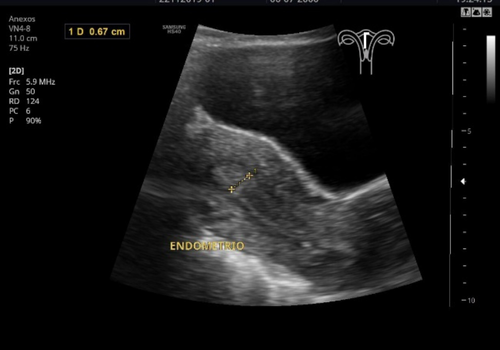

Un ultrasonido pélvico es un examen médico que utiliza ondas sonoras para crear imágenes de los órganos y estructuras dentro de la pelvis femenina. Estas imágenes pueden ayudar a diagnosticar problemas en el útero, ovarios, cuello uterino, vagina y vejiga. También puede ser útil para evaluar el flujo sanguíneo en la pelvis.